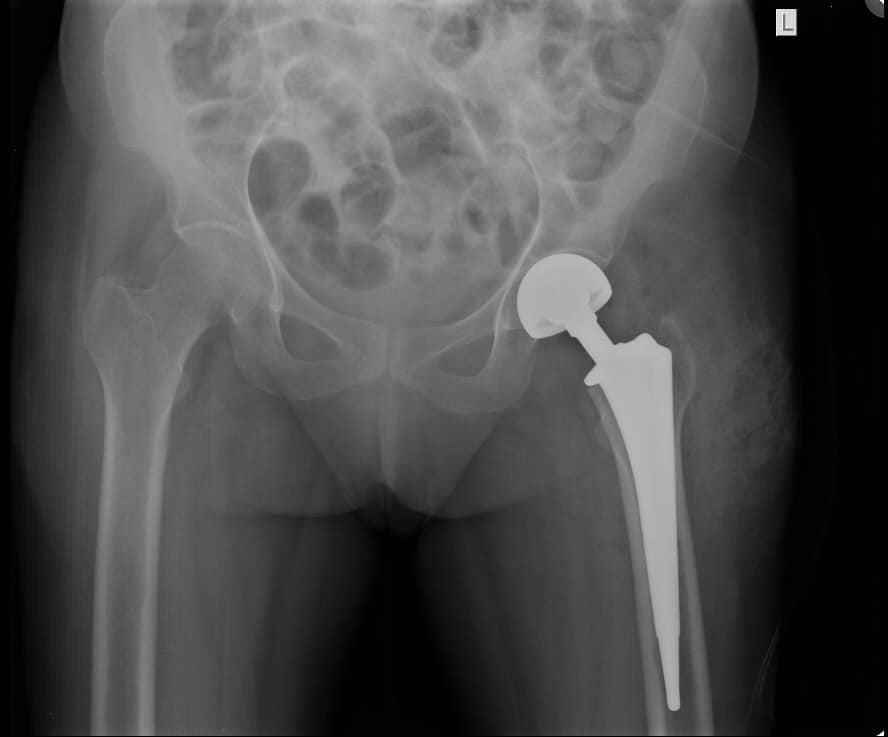

Precision Joint Replacement

Advanced knee, hip, and shoulder replacement procedures tailored to each patient's unique anatomy for optimal results.

Specialized corrective procedures for failed or problematic previous surgeries, restoring proper function and comfort.